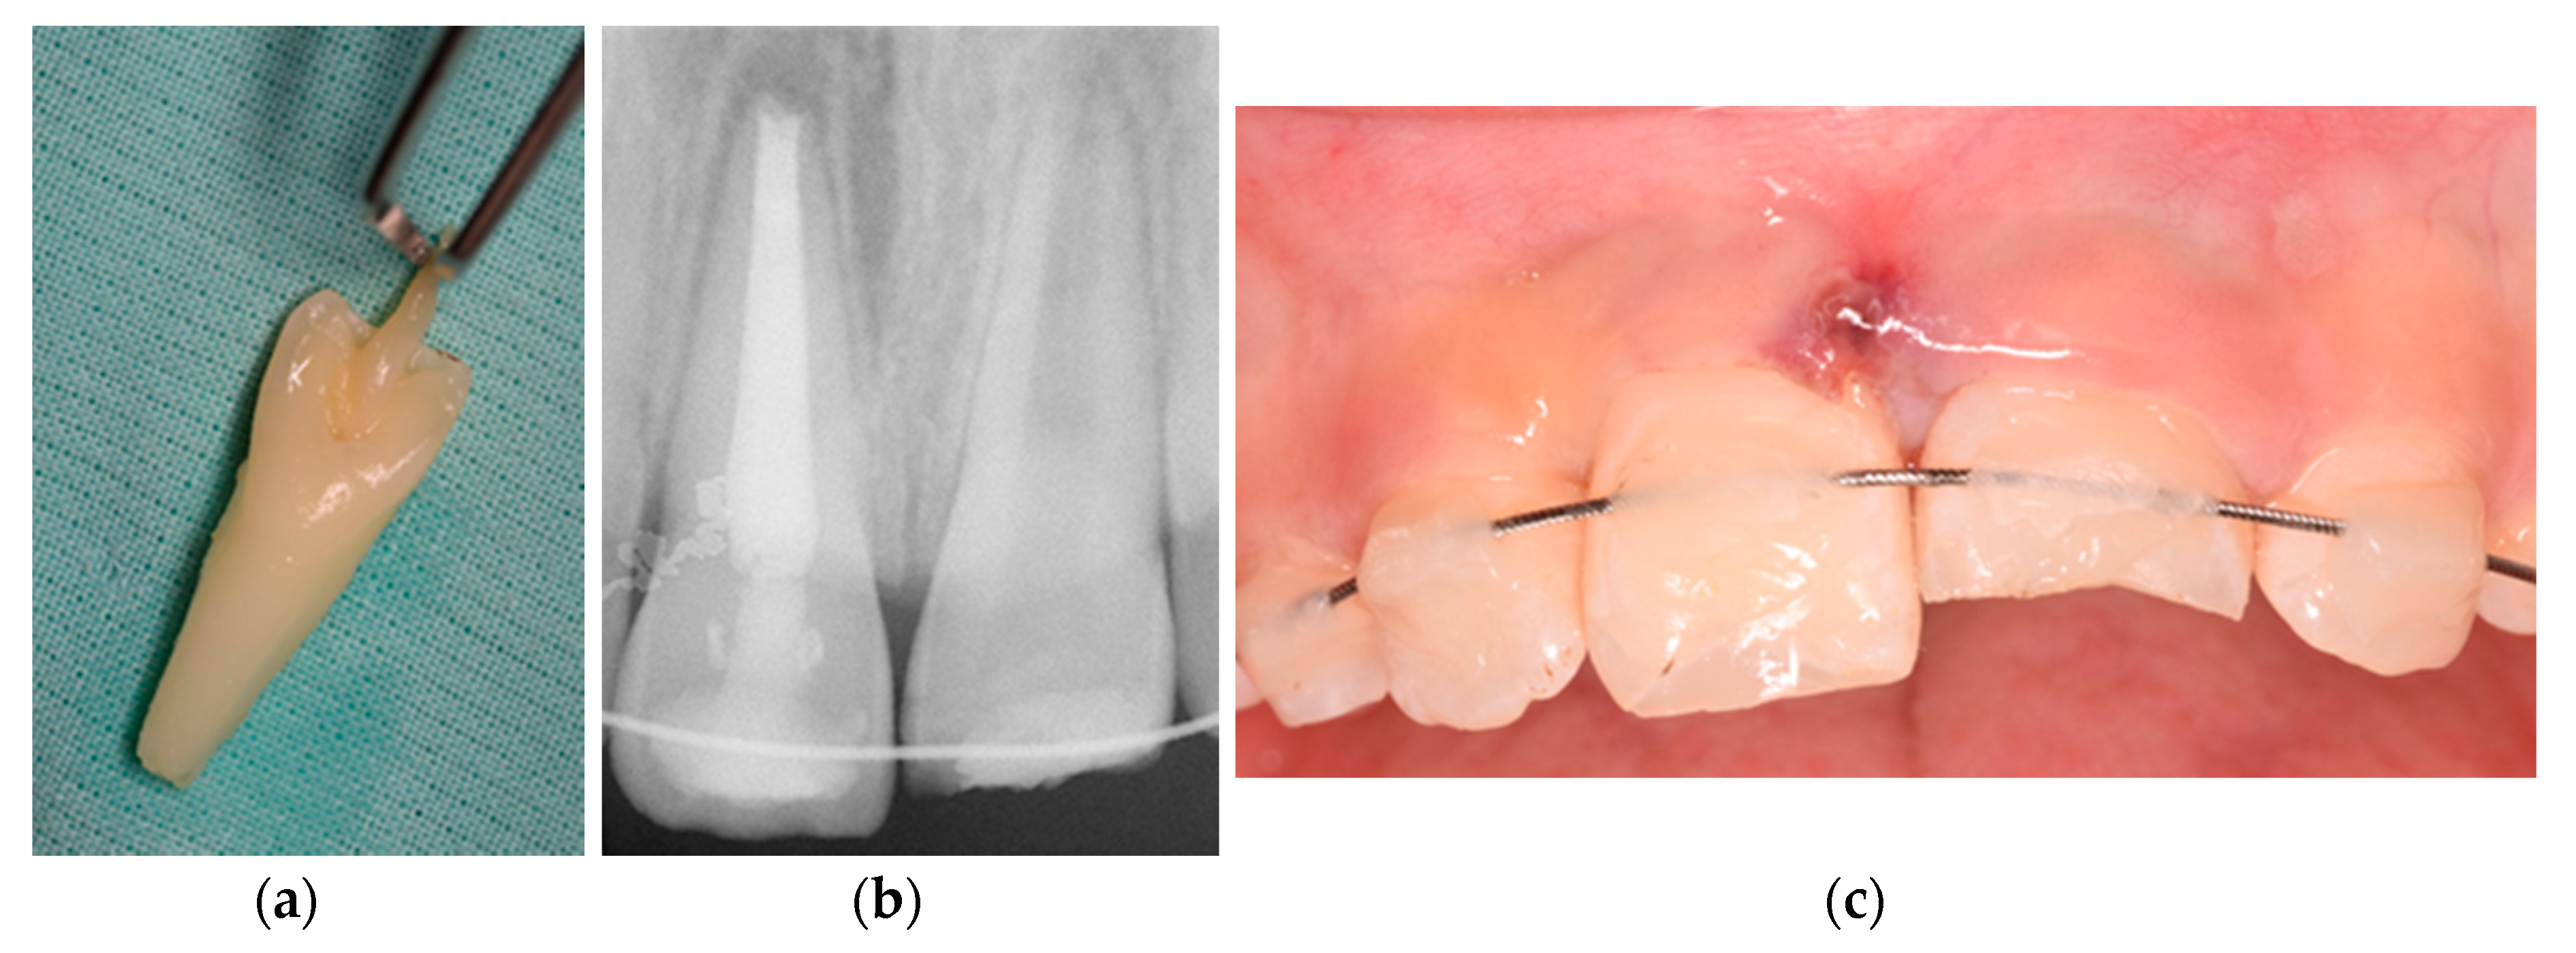

2. Case Presentation